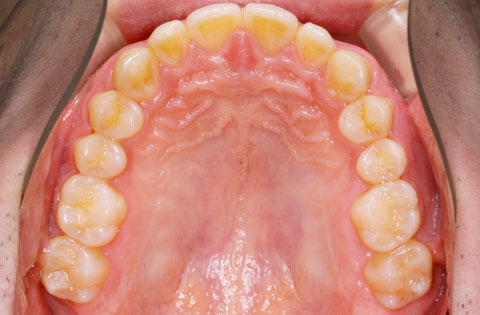

矯正前 上顎

矯正後 上顎